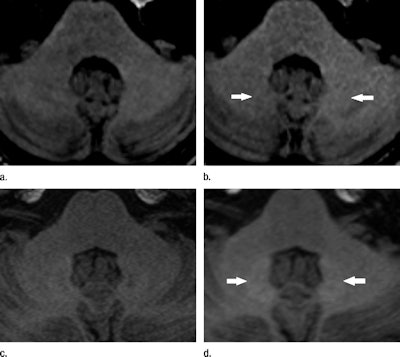

This most recent study follows research by Kanda and colleagues published in January, in which they reviewed 127 patients who underwent brain MRI with gadopentetate dimeglumine or gadoteridol. Two radiologists visually evaluated the area from the dentate nucleus to the cerebellum on unenhanced T1-weighted MRI.

Hyperintensity was found in the dentate nucleus on unenhanced T1-weighted MR images, which the researchers associated with previous administration of gadopentetate dimeglumine. However, there was no hyperintensity in patients who had received gadoteridol.

Lead author Dr. Alexander Radbruch and colleagues from University of Heidelberg Medical Center retrospectively compared signal intensity ratios of the dentate nucleus and the globus pallidus to ratios of other structures on unenhanced T1-weighted MRI.

The researchers found greater signal intensity in the dentate nucleus and globus pallidus on T1-weighted images among patients who received gadopentetate dimeglumine, while there was no such escalation in patients who had received gadoterate meglumine -- despite the fact that a substantially larger dose of contrast was used in the latter group.